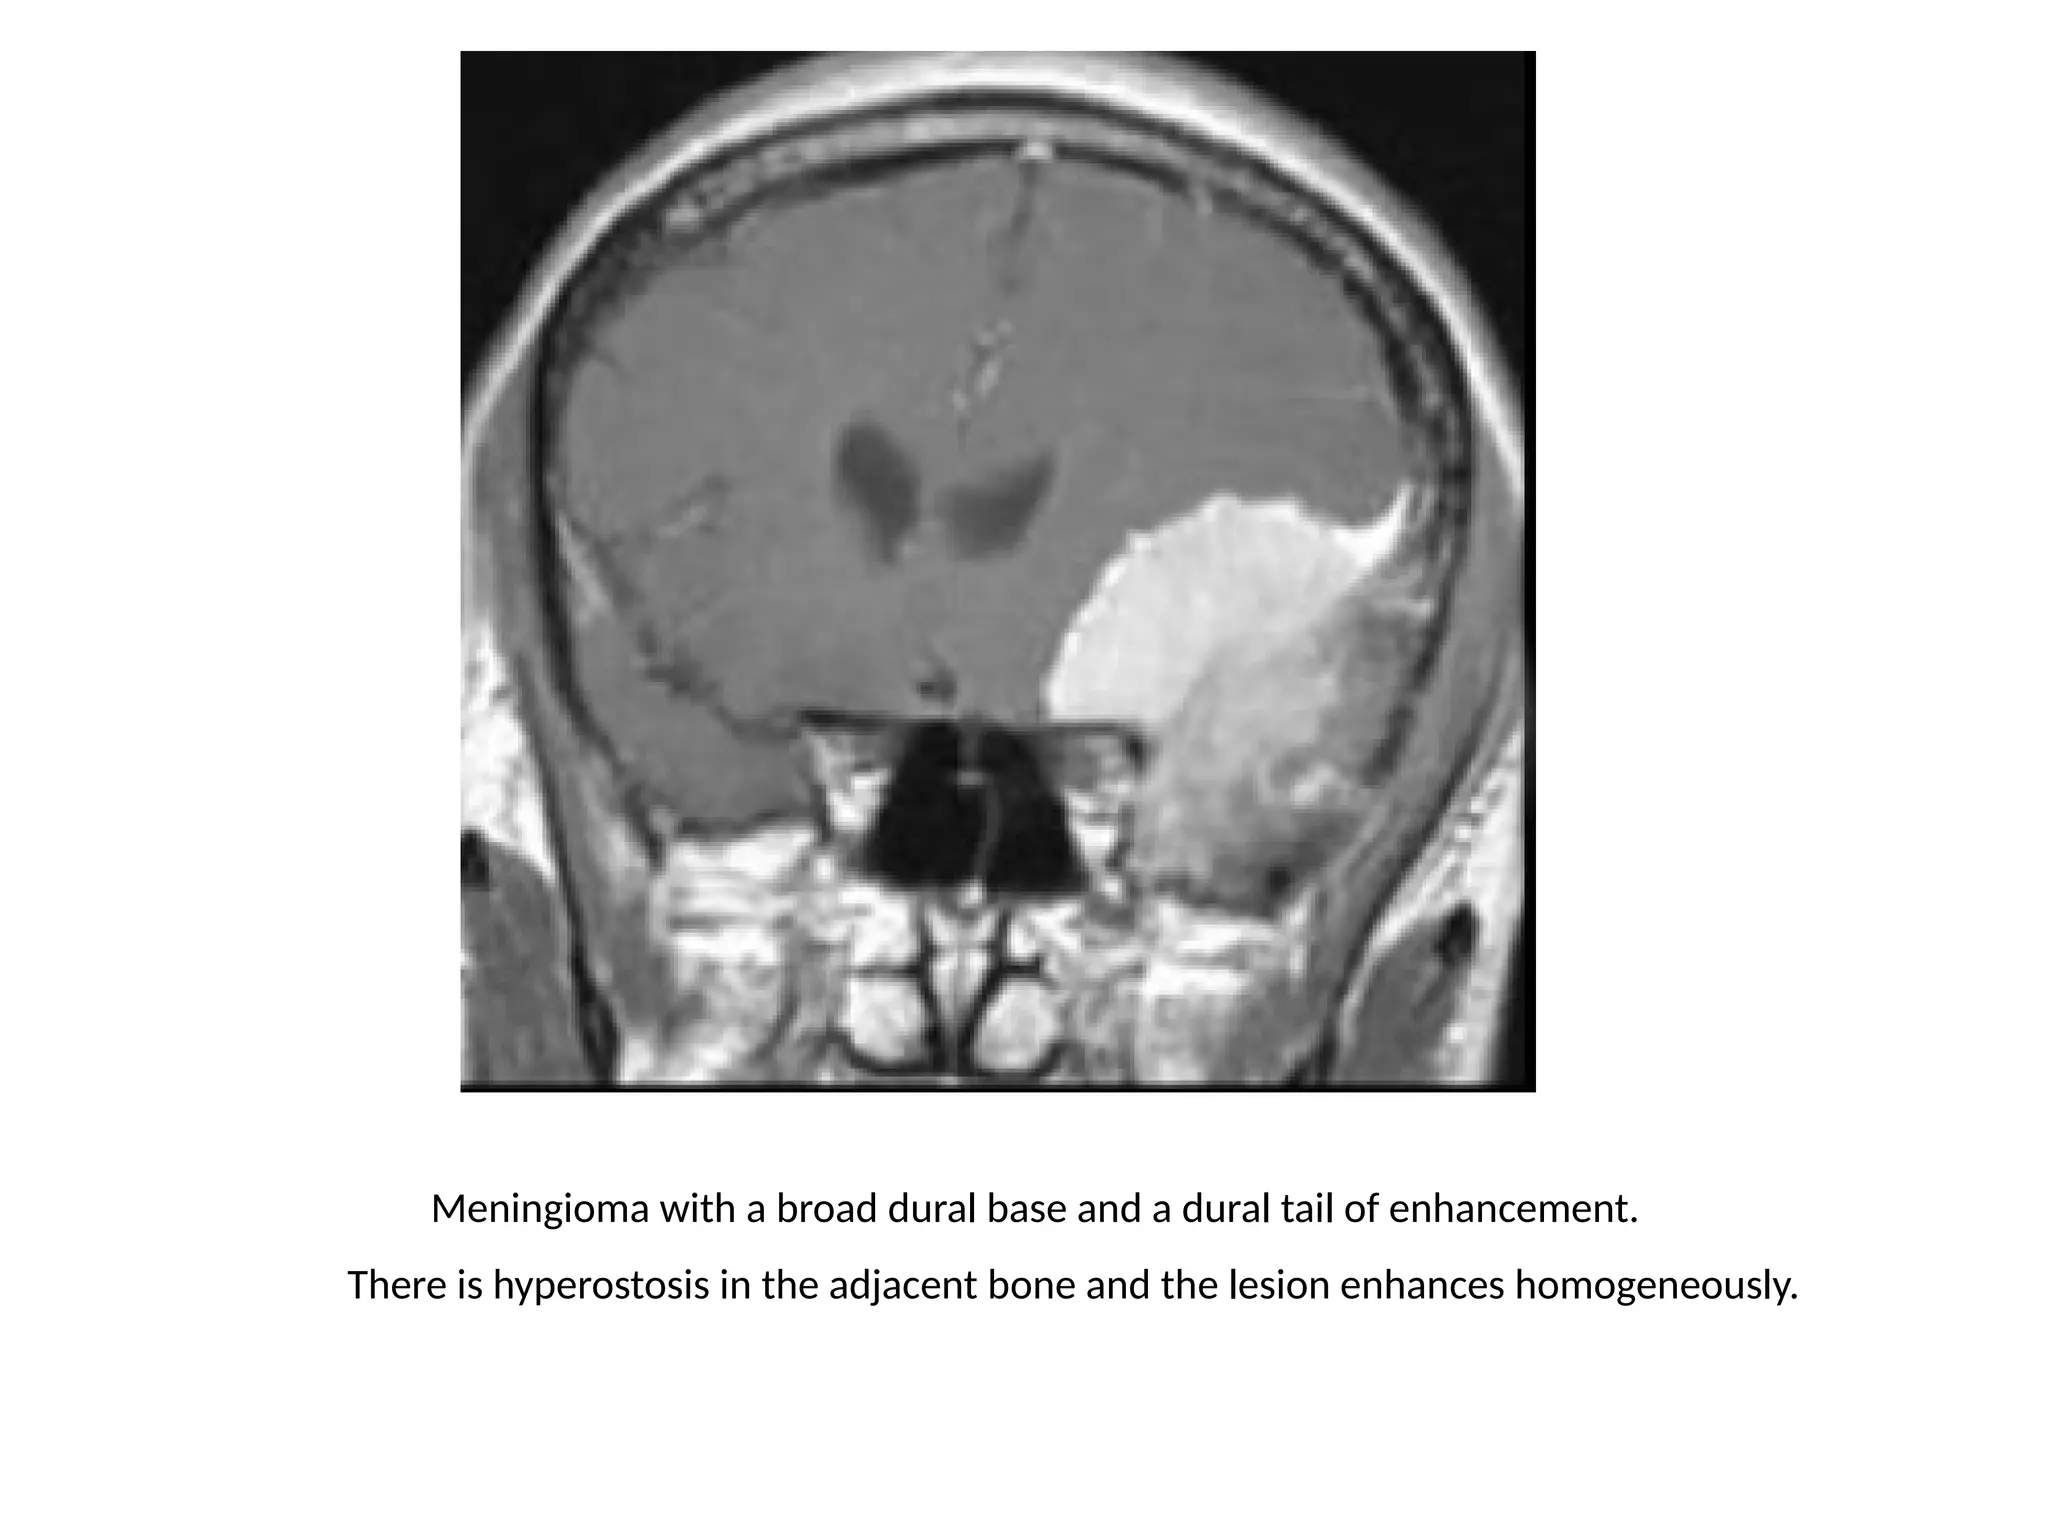

Meningioma with a broad dural base and a dural tail of enhancement.

There is hyperostosis in the adjacent bone and the lesion enhances homogeneously.

Extra-axial tumors are not derived from brain tissue and do not

have a blood-brain-barrier, so most of them enhance

homogeneously.